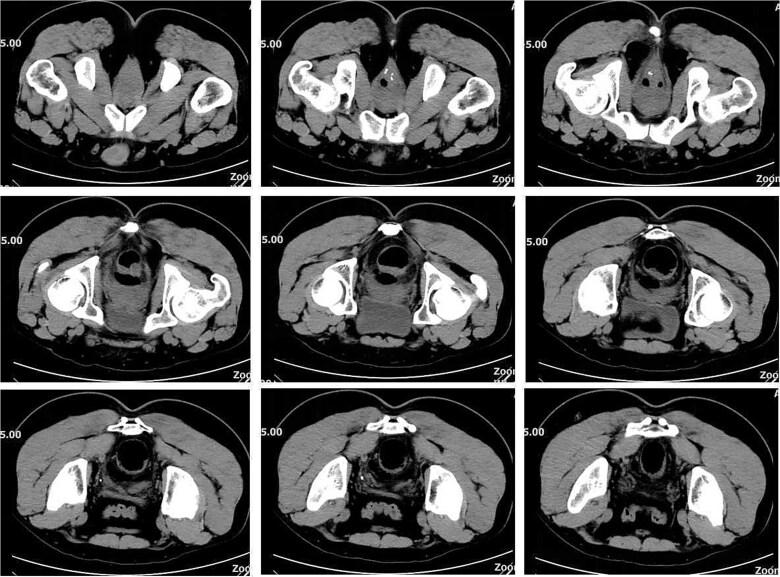

The procedure for prolapse and hemorrhoids (PPH) is designed to reposition displaced anal cushions by circumferential resection of the distal rectal mucosa. PPH offers advantages over traditional excisional hemorrhoidectomy, including less postoperative pain and a shorter hospital stay. However, complications such as anastomotic dehiscence and rectal perforation may occur and require prompt management. This case report presents a patient who developed rectal perforation following PPH, aiming to provide valuable insights for clinical practice.

吻合器痔上黏膜环切术(PPH)的操作旨在通过环形切除直肠远端黏膜来重新定位移位的肛垫。与传统的痔切除术相比,PPH具有术后疼痛较轻、住院时间较短等优点。然而,可能会出现诸如吻合口裂开和直肠穿孔等并发症,需要及时处理。本病例报告介绍了一名在PPH术后发生直肠穿孔的患者,旨在为临床实践提供有价值的见解。